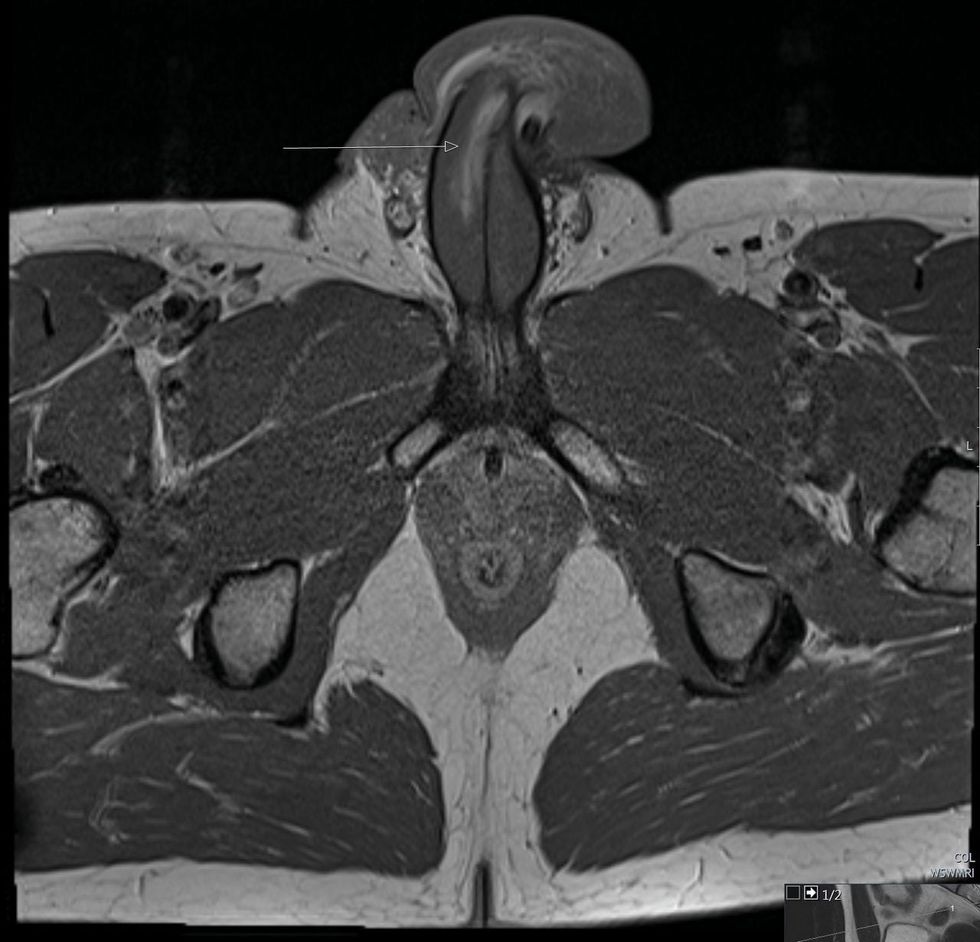

The surgeon confirmed, however, that “indeed there was a 3cm vertical tear” in his snapped penis. This requires surgical intervention within 24-hours to reduce the risk of long-term complications such as “erectile dysfunction, excessive penile curvature or urethral stenosis.”